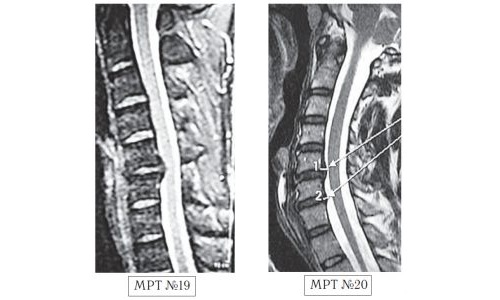

Неверно считать, что рентгенография предоставляет полное представление о данной патологии. Этот метод позволяет лишь оценить состояние твердых тканей. Эффективные способы диагностики при протрузии включают:

- Компьютерную томографию (КТ);

- Магнитно-резонансную томографию (МРТ);

- Миелографию;

- Электромиелографию.

Миелография и электромиелография позволяют оценить состояние спинномозгового канала, степень сжатия и проводимость нервных корешков. Миелография назначается при дорзальной, латеральной, циркулярной или диффузной протрузии. Электромиелография рекомендована для диагностики различных патологий, кроме переднего выпячивания, так как в этом случае образование находится с противоположной стороны от спинномозгового столба.